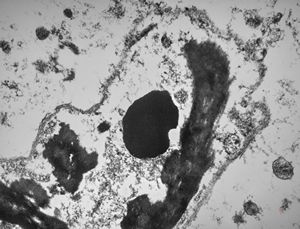

M,11y. | mast cell - skin

M,3y. | mast cell - n. suralis, Krabbe globoid leukodystrophy

F,23y. | mast cell - n. suralis, demyelinating neuropathy